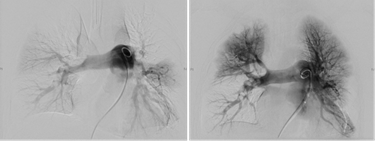

患者在急诊科治疗期间突发心跳呼吸停止,急诊医生给予心肺复苏后,气管插管呼吸机辅助通气,并运用了全身溶栓治疗,但全身状况一直不能好转,急请血管外科、重症监护室、麻醉科等多学科联合会诊,决定对患者进行肺动脉造影+置管溶栓术(Catheter Directed Thrombolysis; CDT)治疗,术前对患者进行了肺动脉CT检查评估,发现该患者双肺动脉主干均有大块栓塞,肺部仅剩五分之一血流畅通,右心扩大,心功能严重受损。情况紧急刻不容缓,经过与患者家属的高效沟通,医生将患者直接从CT室推入手术室,开始了争分多秒的手术。

患者肺部疏通前、后造影对比